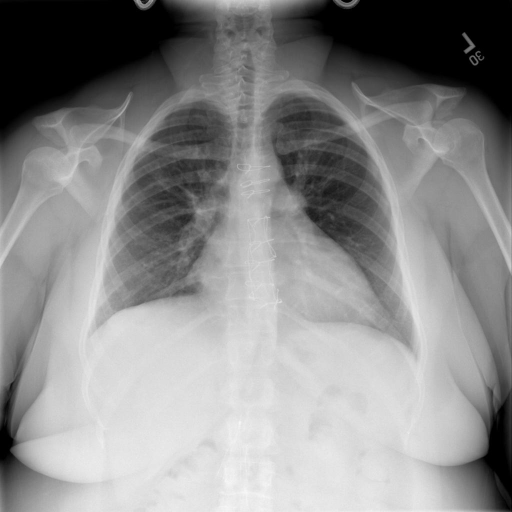

## 本文贡献 ![](./assets/images/xrayglm.png) - 借助ChatGPT以及公开的数据集,我们构造了一个`X光影像-诊断报告`对的医学多模态数据集; - 我们将构建的中文胸部X光片诊断数据集在[VisualGLM-6B](https://github.com/THUDM/VisualGLM-6B)进行微调训练,并开放了部分训练权重用于学术研究; ## 数据集 - [MIMIC-CXR](https://physionet.org/content/mimic-cxr-jpg/2.0.0/)是一个公开可用的胸部X光片数据集,包括377,110张图像和227,827个相关报告。 - [OpenI](https://openi.nlm.nih.gov/faq#collection)是一个来自印第安纳大学医院的胸部X光片数据集,包括6,459张图像和3,955个报告。 在上述工作中,报告信息都为非结构化的,不利于科学研究。为了生成合理的医学报告,我们对两个数据集进行了预处理,并最终得到了可以用于训练的**英文报告**。除此之外,为了更好的支持中文社区发展,借助ChatGPT的能力,我们将英文报告进行了中文翻译,并最终形成了可用于训练的数据集。 |数据集|数量|下载链接| |:-|:-|:-| |MIMIC-CXR-zh|-|-| |OpenI-zh|6,423|[诊疗报告(英文)](./data/openi-en.json)、[诊疗报告(中文)](./data/Xray/openi-zh.json) 、[X光影像](https://pan.baidu.com/s/13GBsDMKf6xBZBSHpoWH_EA?pwd=k9sh)| ## 快速上手 1. 安装环境 ```bash # 安装依赖 pip install -r requirements.txt # 国内换源安装依赖 pip install -i https://mirrors.aliyun.com/pypi/simple/ -r requirements.txt ``` 此时默认会安装`deepspeed`库(支持`sat`库训练),此库对于模型推理并非必要,同时部分`Windows`环境安装此库时会遇到问题。 如果想绕过`deepspeed`安装,我们可以将命令改为: ```bash # 安装依赖 pip install -i https://mirrors.aliyun.com/pypi/simple/ -r requirements_wo_ds.txt # 安装SwissArmyTransformer pip install -i https://mirrors.aliyun.com/pypi/simple/ --no-deps "SwissArmyTransformer>=0.3.6" ``` 2. 模型推理 |模型权重|下载链接| |:-|:-| |checkpoints-XrayGLM-300|-| |checkpoints-XrayGLM-3000|-| CLI推理: ```python python cli_demo.py --from_pretrained checkpoints/checkpoints-XrayGLM-3000 --prompt_zh '详细描述这张胸部X光片的诊断结果' ``` 更多[参数](https://github.com/WangRongsheng/XrayGLM/blob/main/cli_demo.py#L16) ## 效果展示 影像诊断: |X光影像|诊疗报告(医生)|XrayGLM| |:-|:-|:-| |![](./data/Xray/2_1.png)|根据X射线图像,心脏大小正常,肺部看起来很清晰。已经排除了肺炎、积液、水肿、气胸、腺病、结节或肿块的存在。该发现表明一切正常。换句话说,总体印象是胸部正常。|X光片显示,心脏大小正常。肺部没有气胸或胸腔积液的证据。骨骼结构看起来没有任何异常。总的来说,X光片表明没有发现急性心肺疾病的迹象。| |![](./data/Xray/2882_1.png)|X光图片显示没有扭曲的区域、可疑的骨质不透明度或胸腺积液。心脏大小轻微增大,但非常稳定。此外,没有气胸的证据,肺野也正常。总体来说,X光片显示没有急性心脏异常,但要注意轻微的心脏扩大。|X光片显示,心脏大小正常。肺部和纵隔轮廓清晰,没有气胸或胸腔积液的证据。骨骼结构完整,没有任何急性异常。| |![](./data/Xray/2577_1.png)|心影形态在正常范围内。没有急性骨质异常。有可能出现没有明显的吸水或肺实质状况的线索。没有大面积积液或气胸。有可能怀疑其有误吸或肺实质问题。为了确诊和治疗,可能需要进行适当的影像学随访。|心脏大小正常,肺部和纵隔轮廓清晰。没有急性异常或活动受限的证据。没有任何明显的气胸、胸腔积液或肺不张的迹象。此外,也没有发现任何局灶性骨质异常或其他急性疾病。| 多轮对话: |X光影像|诊疗报告(医生)| |:-|:-| |![](./data/Xray/861_1.png)|右侧主动脉突出观察到。心脏大小正常。胸部未发现明显的肺气肿、胸膜积液或可疑的肺部病变。报告指出已知右侧主动脉情况正常。| ```bash >> X光影像路径:./data/Xray/861_1.png >> 用户:这是一张什么图? >> XrayGLM:这张图片显示的是一张肺部检查的X光片。 >> 用户:请描述这张胸部X光片的诊断结果 >> XrayGLM:心脏大小正常,肺部清晰。没有急性心肺疾病的证据。 >> 用户:是否存在肺气肿? >> XrayGLM:没有肺气肿。心脏大小正常,肺部清晰。没有发现急性心肺疾病的证据。 >> 用户:平时饮食该注意什么? >> XrayGLM:饮食应该健康,均衡。建议增加蛋白质的摄入量,因为蛋白质有助于维持肌肉和骨骼的健康。多食用蔬菜、水果、全谷物以及健康的脂肪来源如橄榄油、鱼类等可以帮助获得足够的维生素和矿物质。此外,避免过度饮酒或吸烟,这些习惯可能会对心脏健康产生负面影响。 ``` ## 未来展望 1. 模型的能力更多来源于数据的支持,`OpenI-zh`作为微调数据集,其数据量足以支持研究,在更广泛的任务和性能表现上,我们认为**在大规模数据集上预训练并在高质量少量数据集上微调是一种可行的方案**; 2. 普遍意义的理解上,视觉多模态模型=视觉模型+语言模型。除了需要关注视觉模型信息与语言模型输出的搭配外,还需要**额外关注到语言模型的加强,在人机的对话中,尤其是医疗语言模型的问答上,除了专业的医疗问题回答,带有人文情怀的有温度的回答更应该是我们追寻的目标**。 ## 项目致谢 1. [VisualGLM-6B](https://github.com/THUDM/VisualGLM-6B)为我们提供了基础的代码参考和实现; 2. [MiniGPT-4](https://github.com/Vision-CAIR/MiniGPT-4)为我们这个项目提供了研发思路; 3. ChatGPT生成了高质量的中文版X光检查报告以支持XrayGLM训练; 4. [gpt_academic](https://github.com/binary-husky/gpt_academic)为文档翻译提供了多线程加速; 5. [MedCLIP](https://github.com/RyanWangZf/MedCLIP) 、[BLIP2](https://huggingface.co/docs/transformers/main/model_doc/blip-2) 、[XrayGPT](https://github.com/mbzuai-oryx/XrayGPT) 等工作也有重大的参考意义; ![](./assets/images/mpu.png) 这项工作由[澳门理工大学应用科学学院](https://www.mpu.edu.mo/esca/zh/index.php)硕士生[王荣胜](https://github.com/WangRongsheng) 、[段耀菲](https://github.com/IsBaSO4) 、[李俊蓉](https://github.com/lijunrong0815)完成,指导老师为檀韬副教授、[彭祥佑](http://www.patrickpang.net/)老师。 *特别鸣谢:[USTC-PhD Yongle Luo](https://github.com/kaixindelele) 提供了有3000美金的OpenAI账号,帮助我们完成大量的X光报告翻译工作 ## 免责声明 本项目相关资源仅供学术研究之用,严禁用于商业用途。使用涉及第三方代码的部分时,请严格遵循相应的开源协议。模型生成的内容受模型计算、随机性和量化精度损失等因素影响,本项目无法对其准确性作出保证。即使本项目模型输出符合医学事实,也不能被用作实际医学诊断的依据。对于模型输出的任何内容,本项目不承担任何法律责任,亦不对因使用相关资源和输出结果而可能产生的任何损失承担责任。 ## 项目引用 如果你使用了本项目的模型,数据或者代码,请声明引用: ```bash @misc{wang2023XrayGLM, title={XrayGLM: The first Chinese Medical Multimodal Model that Chest Radiographs Summarization}, author={Rongsheng Wang, Yaofei Duan, Junrong Li, Patrick Pang and Tao Tan}, year={2023}, publisher = {GitHub}, journal = {GitHub repository}, howpublished = {\url{https://github.com/WangRongsheng/XrayGLM}}, } ``` ## 使用许可 此存储库遵循[CC BY-NC-SA](https://creativecommons.org/licenses/by-nc-sa/4.0/) ,请参阅许可条款。